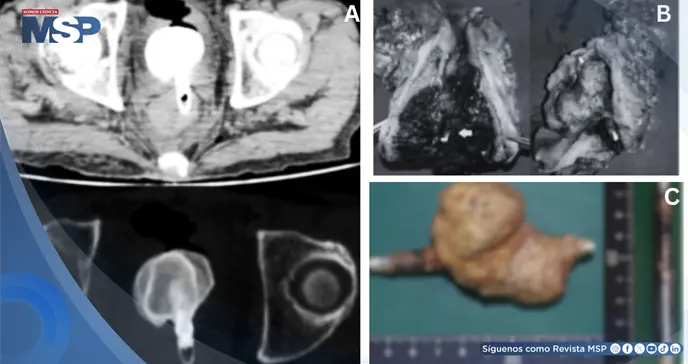

Los estudios mostraron leucocitosis (12.700/µL) y proteína C reactiva elevada (28,36 mg/dL). La tomografía identificó una varilla metálica en región rectal. La inestabilidad hemodinámica impidió cirugía.

La tomografía post mortem mostró un cuerpo extraño penetrando la pared vesical con enfisema intravesical. El examen externo reveló una úlcera perineal crónica de 5 cm rodeada de cambios de coloración cutánea, con el ano intacto.

Internamente se identificó un delineador de ojos de aluminio (9 × 0,8 cm) penetrando la pared rectal anterior hacia la vejiga, con un cálculo vesical gigante de 6,5 × 6,0 × 4,0 cm adherido. La mucosa rectal circundante estaba eritematosa y edematosa. El riñón izquierdo pesaba 250 g, estaba congestivo y rojizo, mientras el derecho pesaba 110 g y lucía pálido. Había hidronefrosis bilateral. El peritoneo permanecía intacto sin signos de perforación.